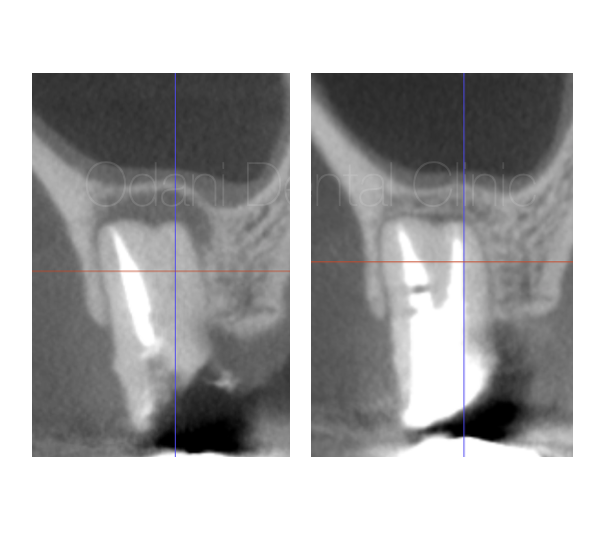

かぶせものの周りに段差があると、「歯ブラシしても汚れが取れない」「磨いても磨けていない」という状況になり、虫歯や歯周病の高いリスクとなります。

患者様は60代女性。以前に装着したかぶせもののやり直し希望で来院されました。かぶせものの辺縁は段差になっており、周囲が少し虫歯にもなってきている状態でした。見た目と適合精度、清掃のしやすさの改善を目的にジルコニアセラミック修復を行うこととなりました。